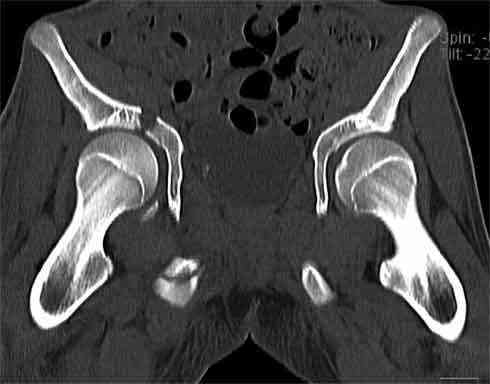

А чего там собственно таинственного? Билатеральное ротационно-нестабильное повреждение таза, перелом крестца в I зоне (по Denis)справа,частичное повреждение левого КПС, оскольчатые переломы лонной, седалищной костей справа (В3.2). Повреждение достаточно стабильное + молодой возраст+ сроки - оперативного лечения не требует.

Не смог разглядеть на представленных картинках частичное повреждение левого КП, повреждение Денис1-2 справа? 3Д реконструкции в инлет и боковой проекциях убедительно не демонстрируют типа повреждения задних отделов тазового кольца(справа боковая масса скомпремирована), Наверное, у тебя есть возможность оценить тип перелома крестца по прямой проекции 3Д.

по Pennal et al.- латеральное компрессионное повреждение тип В(ротационно-нестабильное (внутренняя ротация), вертикально стабильное)

по Tile classif. тип В2-1 - частично стабильное повреждение с неполным разрывом задней дуги.

По вертлуге- смог разглядеть только изолированный перелом передней колонны.

Насколько я понял из твоего письма, обращенного к анонимному vit, ты не видишь показаний к реконструкции перелома. Я бы взялся за реконструкцию(илео-ингвинальный доступ), хоть прошел и месяц после травмы: боковая 3Д показывает смещение нагрузочной зоны впадины, что однозначно будет способствовать разрушению хряща головки и впадины( особенно у 16 летнего пациента с ожидаемым высоким уровнем активности) + изменение геометрии впадины за счет неустраненного смещения фрагментов колонны (КТ, 3Д данные).

На мой взгляд, без реконструкции этот сустав обречен (концепция вторичной конгруэтности в данных условиях работать не будет), реконструкция дает шанс на восстановление функции сустава.

В данном случае 3D и корональные срезы КТ менее информативны, чем поперечные. Согласен с левосторенним минимальным повреждением КПС, но не смог уловить перелом крестца.

По представленным материалам, мне кажется, перелом был передней колонны ацетабулум с минимальным вовлечением нагрузочной поверхности сустава, левосторенний повреждение КПС и лонных костей.

При свежем случае показана фиксация передней колонны к задней (снимки), компрессирующим винтом минимальным перкутанным методом по супраацетабулярной линии и в зависимости от состояния КПС.